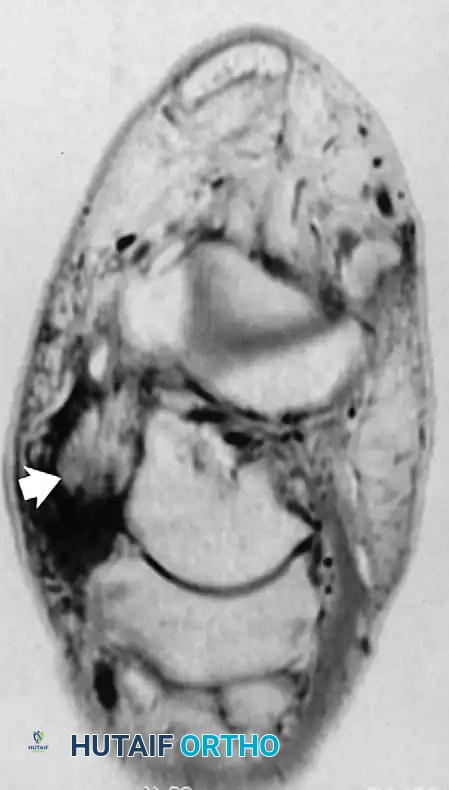

Fig. 2-4 Peroneus longus tendon rupture. A, Coronal T1-weighted image through midfoot shows increased diameter of peroneus longus tendon. B, Coronal fat-suppressed, T2-weighted image reveals fluid signal within ruptured tendon.